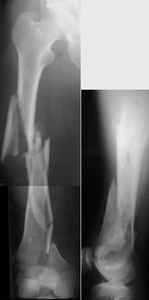

KEMMD> (Alex, do you have one good case in your collection of

KEMMD> anterograde nailing in very distal fractures - as you have

I presented a series of ~25 such cases at EuroTrauma'2004. Many cases were discussed here. I attach am example. Look also recent cases at http://www.hwbf.org/hwb/conf/alex58/scfx.htm,

http://www.hwbf.org/hwb/conf/alex63/alex63.htm